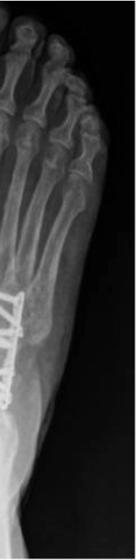

921 Charcot Neuroarthropathy of the Foot and Ankle in the Acute Setting: An Illustrative Case Report and Targeted Review

Duringthestudyperiodatotalof21participants comprising19residents(sixpostgraduateyear[PGY]1,